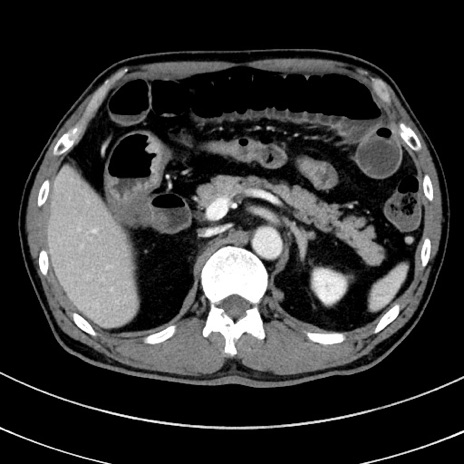

症例8(横断像)

【症例】 60歳代男性

【主訴】 黒色吐物

【現病歴】 4日前から嘔気自覚、2日前の朝食後にも嘔気あり、自分で手で嘔吐反射起こし嘔吐したところ血が混ざっていたため受診。

【既往歴】 5年前汎発性腹膜炎を伴う急性虫垂炎で手術、高血圧、前立腺肥大症、高脂血症

【身体所見】 腹部正中に手術癩痕あり 腹部平坦・軟圧痛なし膨満感あり

【データ】WBC 8400、CRP 4.54